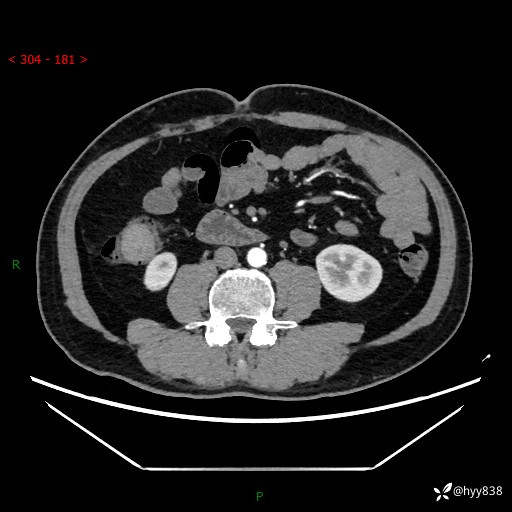

腹部CT增强扫描(外院CT平扫)

两期CT值:75hu 82hu